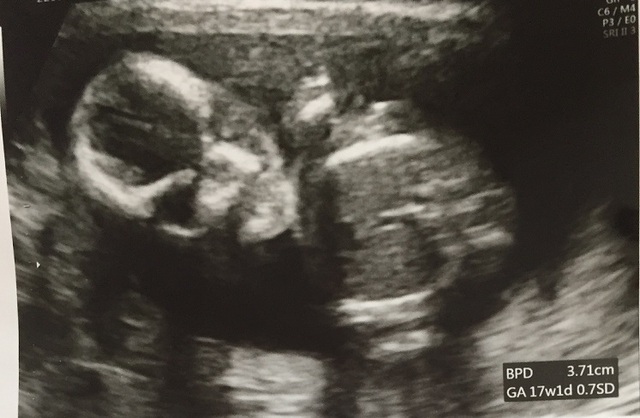

17週0日(17w0d・性別不明)|a.n.a さん(27歳)

エコー写真撮影時のエピソード:

妊娠16週中に急な吐き気と嘔吐があり、ツワリ再発?!と思いきや、胃腸炎でした!食べ物には気をつけていましたがウィルスには勝てませんでした(;ω;)病院で点滴をしてもらい心配だったのでエコーで赤ちゃんも見せてもらいました。その時はまだなんとなくいるなーって感じで先生が元気だと言うから元気なのだろうという感じでしたが、17週に入った健診で改めてみた我が子は急成長!!正直この時に初めてあー本当に私の中で生きてるんだなーと実感しました。舌をペロペロしたり大きな口を開けたり元気な子で安心したそんな1枚です。